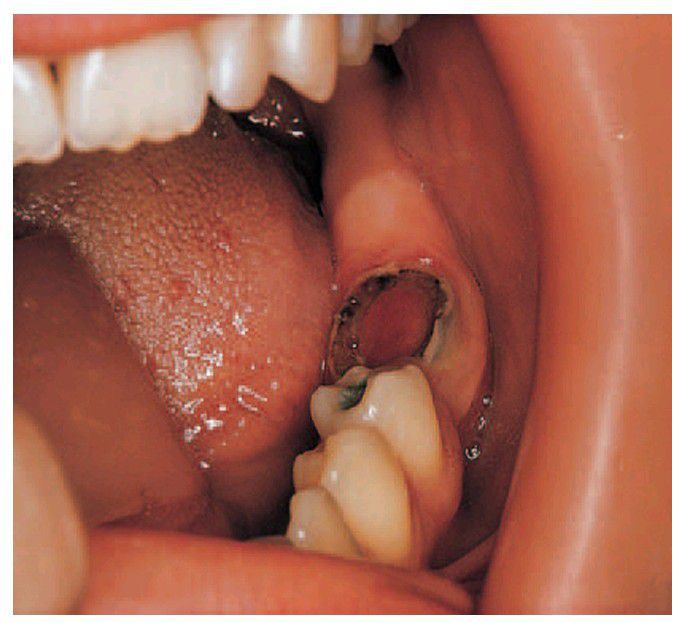

Pulp polyp.

An infl amed nodule of granulation tissue can be seen growing from the pulp chamber of this broken down fi rst permanent molar.